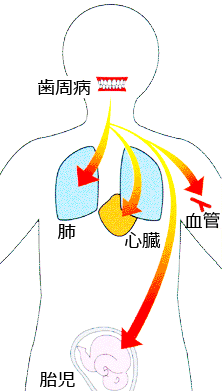

歯周病が及ぼす全身への悪影響

心疾患:

重篤な歯周疾患に罹患している患者は、心筋梗塞のリスクが高いことが明らかになっています。

歯周炎患者が心筋梗塞や脳卒中を発症するリスクは、歯肉健常者の1.5~ 3 倍、冠状動脈疾患発症率は2倍です。

未熟児(2500g未満)・早産(37週未満):

妊婦の歯周病が原因となり、未熟児や早産が起こりやすくなします。

歯周疾患の既往している妊婦の早産・未熟児出産の確率は健常者と比較して7倍です。

糖尿病:

糖尿病患者は、統計的に歯周疾患を既往している率が高く、糖尿病併発症として歯周疾患は6番目に位置付けられています。

糖尿病が歯周病を含めた感染症を悪化させることはよく知られていますが、歯周病も糖尿病を悪化させます。歯周病の治療・管理により1型・2型を含めた糖尿病患者では、歯周病の治療を行うことでHbA1cが平均0.4%改善するという報告もあります。

呼吸器系疾患:

細菌性の呼吸器系感染症は、口腔内や気管の水分を肺に取り込むことで生じると考えられています。

これらの水分には細菌が含まれ、肺の中で増殖し、ダメージを与えます。

喉(のど)の細菌や口腔内の細菌が深部肺胞で検出されたとの報告もあります。

これにより誤嚥性肺炎を引き起こします。